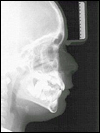

| Handwurzelaufnahme zur Bestimmung der individuellen Reife des Patienten | Fernröntgenseitenbild (FRS) zur Beurteilung der Kieferbeziehung aus seitlicher Sicht |